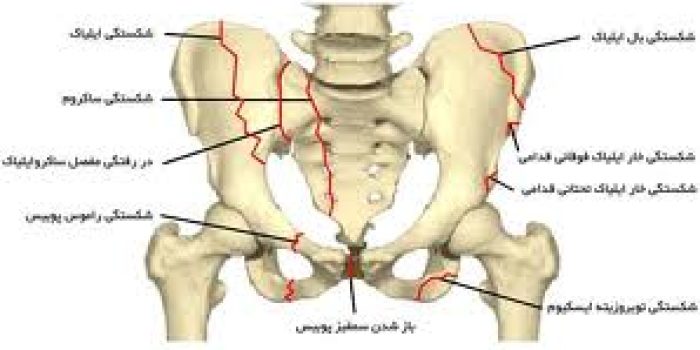

همانطور که اشاره شد، در آسیبهای ناپایدار حلقه لگن، معمولاً آسیب قدامی به صورت شکستگی راموس های پوبیس یا جداشدگی دو استخوان بینام در محل سمفیز پوبیس رخ میدهد. همچنین، آسیب خلفی (پشت) لگن نیز معمولاً به صورت شکستگی استخوان ایلیاک، رفتگی مفصل ساکروایلیاک (مفصل بین استخوان ایلیاک و ساکروم) یا شکستگی استخوان ساکروم ایجاد میشود.